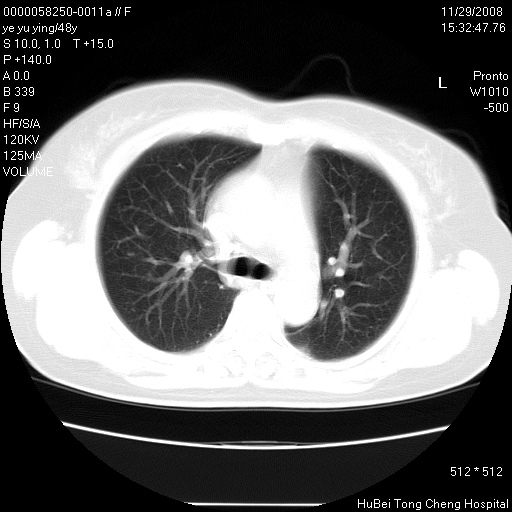

以下是引用zsl6918在2008-11-29 21:47:00的发言:[br]恶性肿瘤病史,转移瘤首先考虑。脂肪肝,胆囊结石。

以下是引用huenhao在2008-11-29 22:11:00的发言:[br]脂肪肝,胆囊结石。左肺病灶建议定期复查。

以下是引用liuyue在2008-11-30 5:44:00的发言:[br]1.左肺病变,首先考虑感染性病变,转移待排;建议治疗后复查。[br]2.肝脏密度普遍减低,考虑与化疗有关。[br]3.胆囊结石.